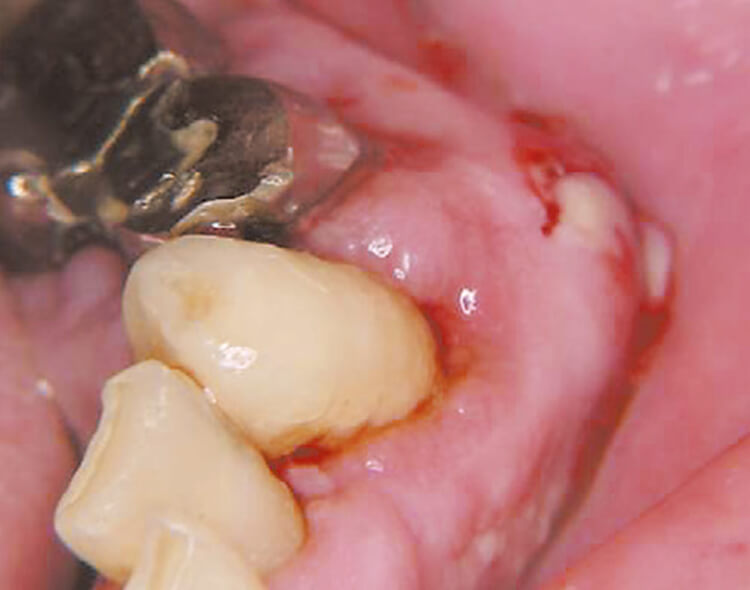

歯肉切除

10pps80mJ、20pps40mJ。押し付けてきるのではなく、あくまでもレーザー光に仕事をさせるのが肝要です。この症例ではS600Tではなく、C400Fを使用していますが、症例によりチップ選択が多様になります、当然P400Tも選択肢に入ります。